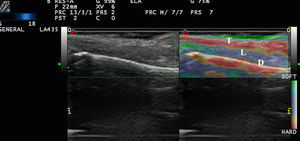

Elastografía de la piel normal y los anejosLa dureza de la piel sana varía en función del estrato cutáneo estudiado. La dermis es una estructura de rigidez superior al tejido celular subcutáneo16 (figs. 2a,b). En el tejido celular subcutáneo, los septos presentan mayor rigidez que los lobulillos grasos. Los vasos sanguíneos son estructuras poco rígidas, al igual que los nervios periféricos, en comparación con el tejido celular subcutáneo circundante16.

a) Elastografía de strain de la piel normal. Obsérvese el ratio de rigidez de dermis y la grasa SR=1,86 que indica que la dermis es más dura que el tejido celular subcutáneo.

E: epidermis; D: dermis; TCS: tejidocelular subcutáneo.

b) Elastografía SW de la dermis del cuero cabelludo. Obsérvese en la esquina inferior derecha los parámetros de velocidad y presión de la región de interés analizado (rectángulo verde-amarillento).

En la uña sana, la tabla ungueal es rígida en comparación con el lecho ungueal 17 (fig. 3).